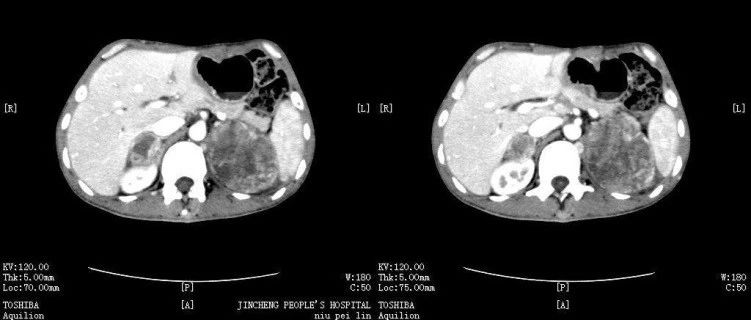

*仅供医学专业人士阅读参考这个病你能想到吗?病例简介患者中年女性,规律维持性腹膜透析7年余,反复关节疼痛伴胸闷、气促1年余。既往史:既往有"癫痫"病史10余年,混合痔病史1年余,多次骨折病史。体格检查:体温:36.5℃ 脉搏:84次/分 呼吸:20次/分 血压:174/105mmhg神志清楚,慢性病容,贫血貌,双肺呼吸音粗,双下肺可以闻及少量湿性啰音。心率84次/分,心律齐,各瓣膜区无杂音。腹部平坦,腹壁柔软,无压痛,无反跳痛。Murphy征阴性,肝脏、脾脏未触及,移动性浊音阴性,双侧肾区无叩痛,肠鸣音正常,4次/分,双侧下肢重度凹陷性浮肿。...